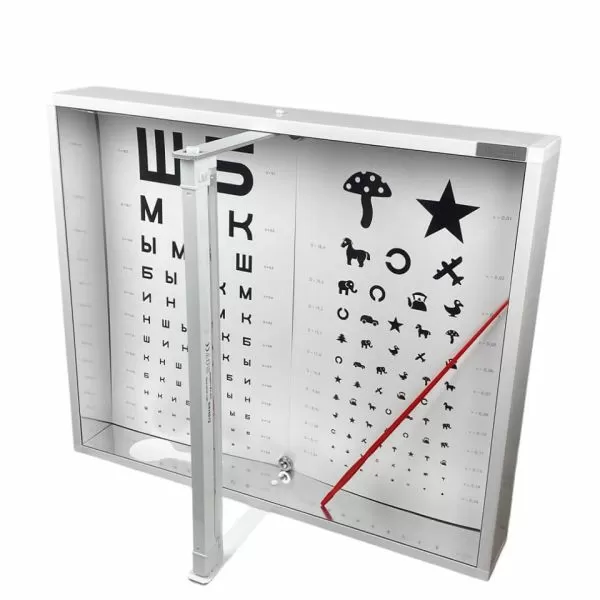

Арт.: Ш4 FS1

4 830 руб./шт

Арт.: 9001LED

8 835 руб./шт